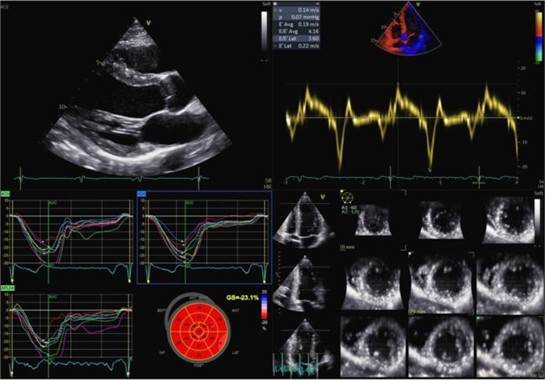

Metodiche di imaging nel real-world per di migliorare la sicurezza degli atleti: opportunità e limiti 👉 cardiologianegliospedali.it/imaging-nel-cu…

_anmco's tweet image. Metodiche di imaging nel real-world per di migliorare la sicurezza degli atleti: opportunità e limiti

👉 cardiologianegliospedali.it/imaging-nel-cu…